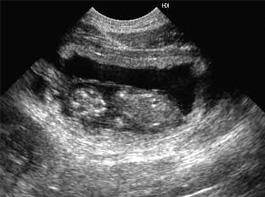

Первые признаки того, что беременность у кошки наступила, начинают появляться примерно на 3 неделю после оплодотворения – увеличение веса и аппетита, увеличение размеров и усиление розовой окраски сосков. До этого времени животное часто бывает наоборот, менее активно, аппетит и активность могут быть снижены, что часто приводит владельцев к ложным выводам о возможном заболевании. Начиная с 2-3 недельного срока беременность кошки можно подтвердить по УЗИ.

Для кормления беременной кошки нужно применять специальные корма для беременных, правильное кормление поможет хорошо развиваться будущим котятам. За 3-4 дня до родов желательно сделать УЗИ, для определения количества и размеров плодов – это поможет спрогнозировать течение беременности (иногда котята бывают слишком крупные – в таком случае решается вопрос об операции).